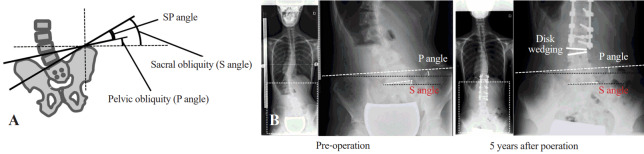

Methods: Data from 35 patients with Lenke type 5 AIS (mean age, 14.7±1.8 years) followed for a minimum of 5 years were retrospectively analyzed. We investigated the effect of sacral coronal obliquity (S angle) and pelvic coronal obliquity (P angle) on postoperative coronal radiographic parameters. The angle between the S and P angles was defined as the sacral and pelvic (SP) angle. The patients were grouped by preoperative SP angle (<5°, n=23; ≥5°, n=12). Pre- and post-operative radiographic parameters were compared to determine whether the preoperative SP angle affected postoperative spinal alignment.

Results: The discrepancy between SP obliquity was reduced by correction surgery 5 years postoperatively. The mean lumbar Cobb angle correction rate in the ≥5° group was significantly lower than that in the <5° group (52.1%±17.8% vs. 65.5%±12.7%), and the mean wedge angle below the lower instrumented vertebra (LIV) in the ≥5° group was significantly larger than that in the <5° group (9.0°±2.6° vs. 4.7°±3.4°) 5 years postoperatively. No significant between-group differences were observed in age, Risser grade, thoracic Cobb angle correction rate, LIV-central sacral vertical line (CSVL), and C7-CSVL. The Scoliosis Research Society-22 outcomes were comparable between the two groups.

Conclusions: The ≥5° group exhibited a larger wedge angle below the LIV and lower lumbar Cobb angle correction rate than the <5° group 5 years postoperatively. Preoperative discrepancies between SP obliquity should be considered when planning corrective surgery for patients with Lenke type 5 AIS.